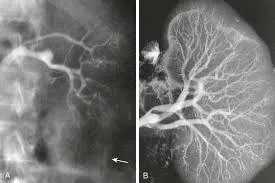

**CONGESTÃO VEIA RENAL**

Em pacientes com cirrose descompensada, uma causa de IRA pode ser a congestão da veia renal secundária à hipertensão intra-abdominal causada pela ascite e insuficiência cardíaca direita. Além de modelos em bancada que demonstram um aumento da liberação de óxido nítrico e lesão endotelial, é descrito aumento do débito urinário e do clearance de creatinina após redução da pressão abdominal que ocorre após realização de uma paracentese.